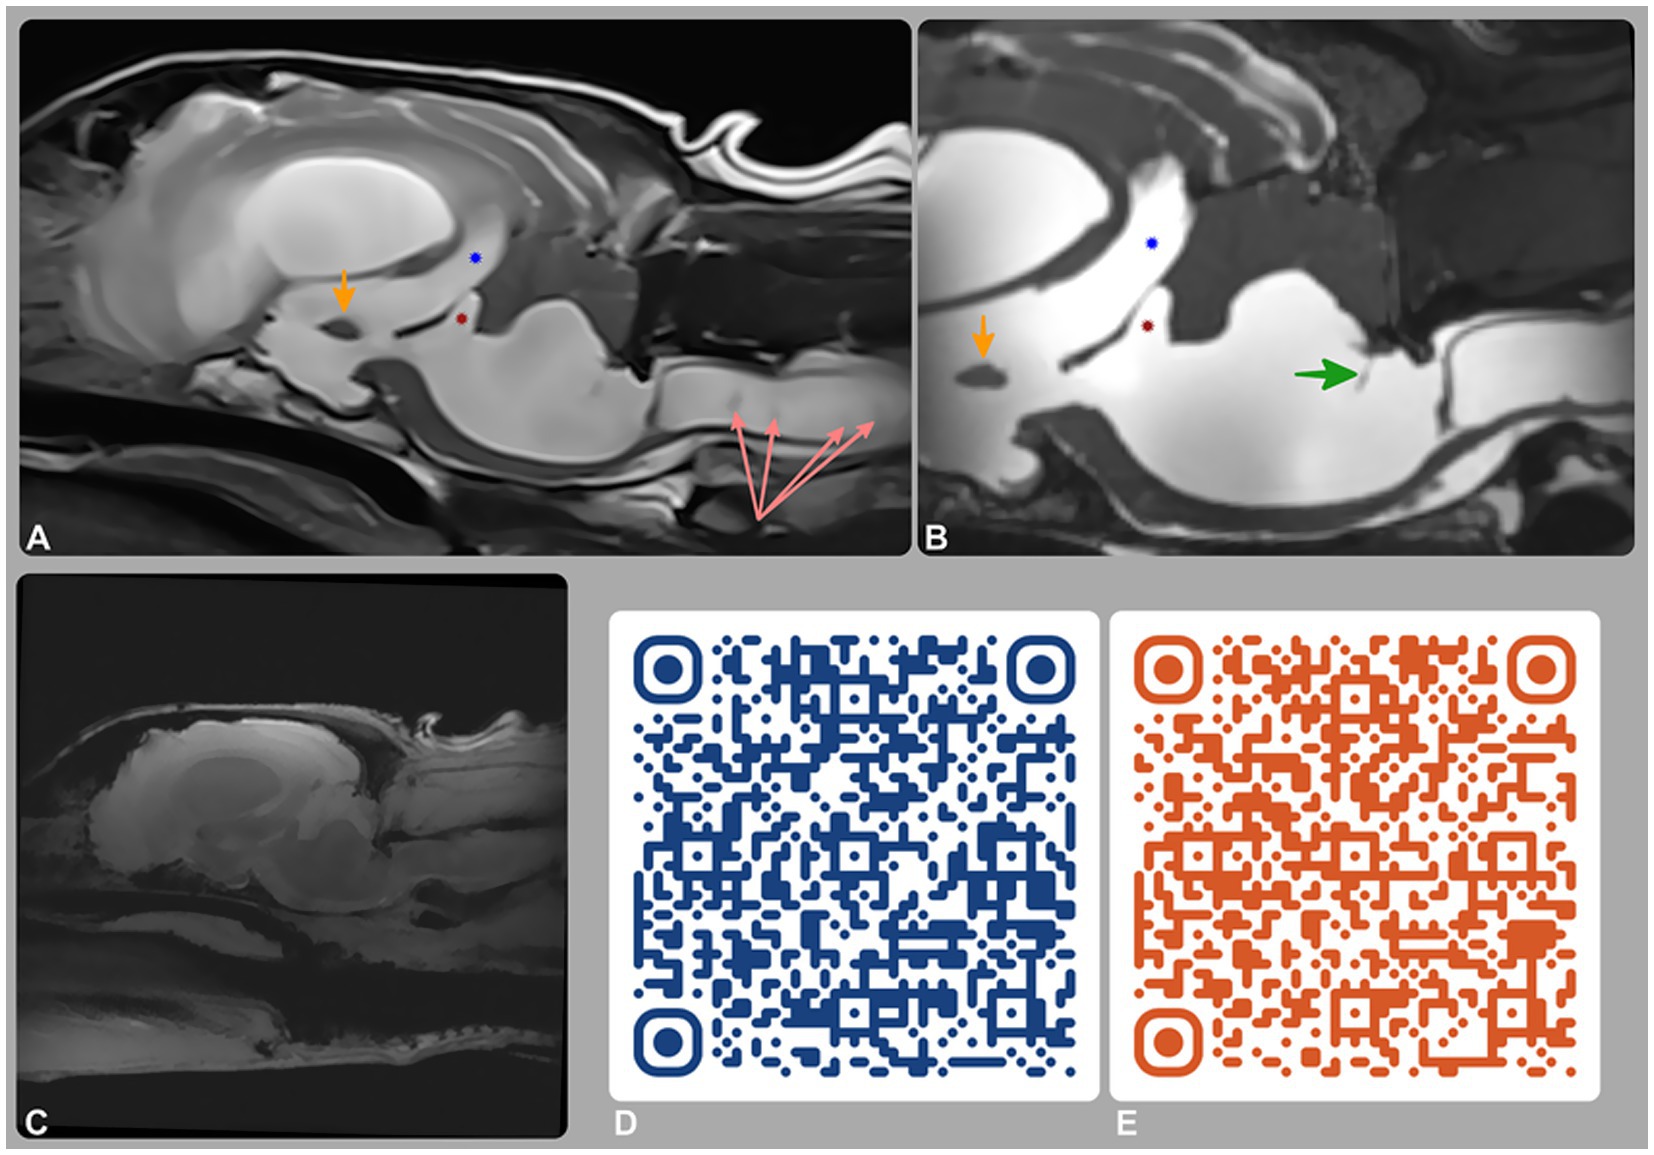

Figure 1. Magnetic resonance imaging (MRI) of the brain and cervical spine. (A) T2-weighted and (B) 3D-CISS mid-sagittal images; (C–E) phase-contrast MRI (PC-MRI), including a re-phase image (C) and QR-code-linked videos of the magnitude (D) and phase (E) sequences. MRI showed tetraventricular hydrocephalus, supracollicular fluid accumulation, and third (blue star) and fourth (red star) ventricle dilation. A membrane within the fourth ventricle (green arrow) represents a stretched rostral medullary velum. CSF flow was preserved intraventricularly but absent at the lateral apertures on PC-MRI, consistent with partial or complete obstruction.

MRI findings (Figures 1A,B) revealed severe, diffuse dilation of the entire ventricular system, including the lateral ventricles and olfactory recesses, third ventricle, mesencephalic aqueduct, fourth ventricle, and lateral recesses (Figure 2). Additional findings included flattening of the interthalamic adhesion, compression of the cerebellum and brainstem, and supracollicular fluid accumulation with concurrent expansion of both the third ventricle and the quadrigeminal cistern. Within the ventricular system and the syrinx, hyperintensity on FLAIR and mild signal voids on T2w images were consistent with rapid and turbulent CSF flow. A thin band isointense to gray matter on both T1w and T2w images was observed along the dorsal and lateral aspects of the caudal portion of the fourth ventricle. Moderate periventricular hyperintensities on T2w and FLAIR images were consistent with hydrostatic interstitial edema. Effacement of the cerebral sulci was noted, along with dorsal displacement of the corpus callosum and partial absence of the septum pellucidum. At the level of the cervical spine, moderate scoliosis and severe syringomyelia were identified, accompanied by extensive spinal cord edema extending throughout the cervicothoracic region. No abnormal parenchymal or meningeal enhancement was observed following contrast administration. The ventricle-to-brain (VB) index, assessed on dorsal T2w images, was 0.69 (reference interval < 0.6) (14).

A repeat brain MRI (Figures 1C–E) was performed to assess disease progression and assist with surgical planning. Advanced imaging sequences included 3D-Constructive Interference in Steady State (3D-CISS) and Phase-Contrast MRI (PC-MRI). Full acquisition parameters, including flip angle, voxel size, field of view, and gating strategy, are reported in Supplementary Table 1. These sequences provided high-resolution anatomical detail and enabled CSF flow evaluation using re-phase, magnitude, and phase images.

MRI findings revealed progressive loss of parenchymal volume, with an increase in VB index to 0.82 (RI < 0.6). A thin membrane within the fourth ventricle, better visualized on 3D-CISS, corresponded to the rostral medullary velum—a normal anatomical structure that becomes more conspicuous with ventricular dilation and altered anatomy, rather than a pathological septation or diverticulum. PC-MRI, together with conventional sequences and anatomical landmarks, demonstrated preserved intraventricular CSF flow but no signal to suggest outward flow from the region of the lateral apertures, supporting this location as the site of obstruction. These findings excluded a fourth ventricle arachnoid diverticulum and supported a diagnosis of obstructive hydrocephalus, most likely secondary to lateral aperture occlusion.

In the case described, PC-MRI confirmed patency of intraventricular CSF flow and suggested impaired flow at the level of the lateral apertures (Figures 1C–E). Although a CSF velocity study using a quantitative flow analysis at the lateral apertures might have provided more definitive insight, this was not possible due to the lack of the post-processing software.

The 3D-CISS sequence is known for its high-resolution imaging of CSF spaces and surrounding anatomical structures (30, 31). The dorsal surface of the pons and medulla is normally covered from rostral to caudal by the rostral medullary velum, the cerebellum, and the caudal medullary velum (8). In this dog, a thin membrane within the fourth ventricle was most likely part of these normal structures, which dorsally bound the ventricle and attach to the cerebellum and its meningeal coverings. With severe ventricular dilation, these membranes became more conspicuous on MRI due to displacement and CSF accumulation, rather than representing a new or abnormal septating membrane (Figure 1B). This interpretation was supported by the complementary findings on PC-MRI.